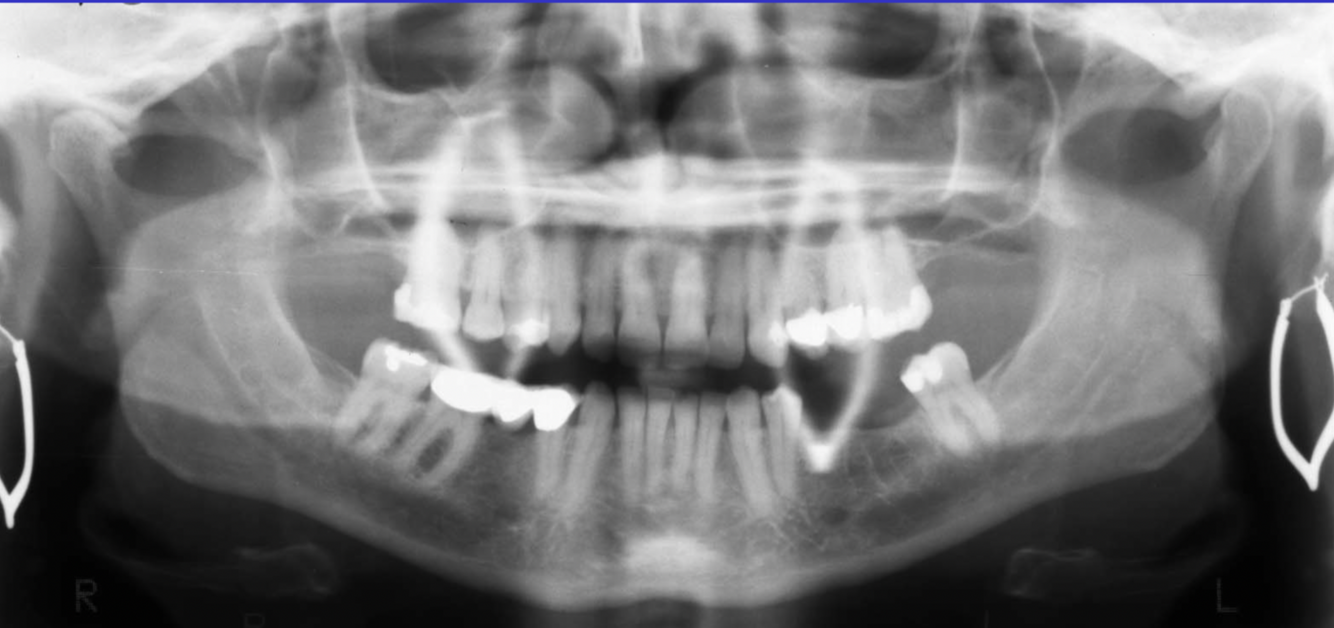

What errors can be seen in the following radiograph? What is the cause?

1. excessive curvature of the occlusal plane 2. roots of mandibular anterior teeth are blurred 3. rami/condyles tipped inward 4. condyles close to or cut off top of image 5. hyoid bone superimposed on mandible cause: chin down